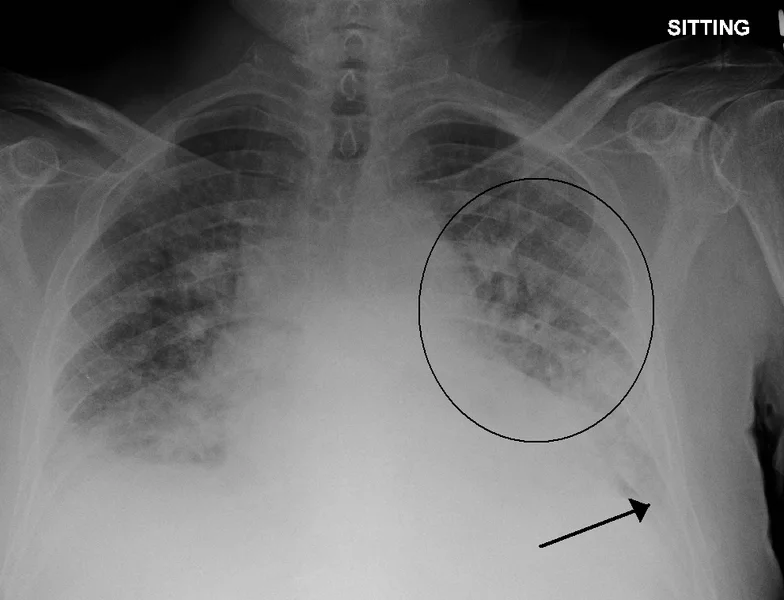

A new machine learning algorithm was shown to be capable of classifying severe cases of pulmonary edema with high accuracy

In putting it to the test, the team had the machine learning algorithm analyze single X-ray images and classify the severity of edema, ranging from 0 (healthy) to 3 (very, very bad). The algorithm was able to diagnose the correct level of edema more than half the time, but more impressively, was able to accurately diagnose level-3 cases 90 percent of the time.